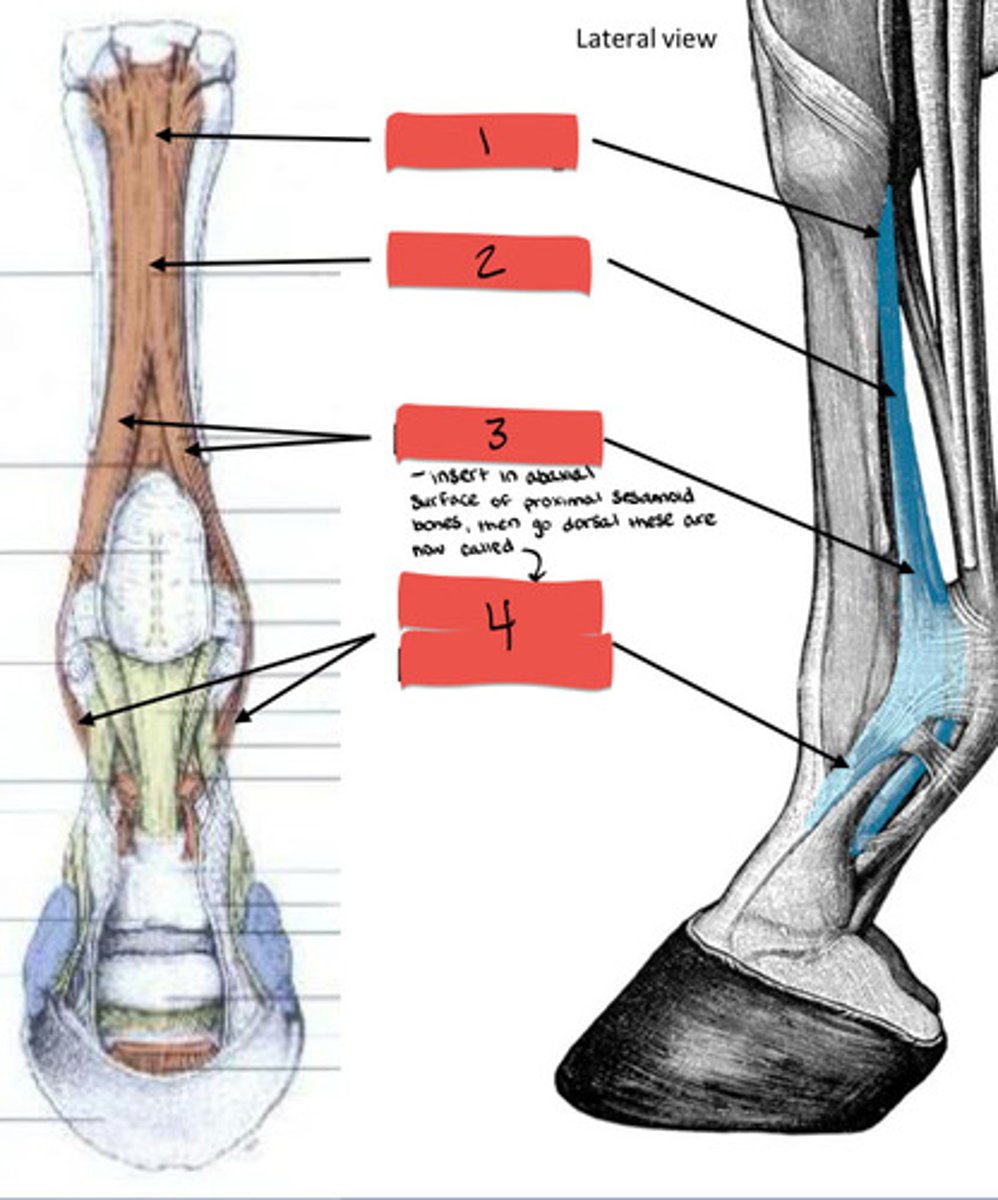

Common digital extensor muscle

What is 1?

Common digital extensor tendon

What is 2?

Lateral digital extensor tendon

What is 3?

Lateral digital extensor muscle

What is 4?

Proximal

Mid-body

Branches

Extensor branches